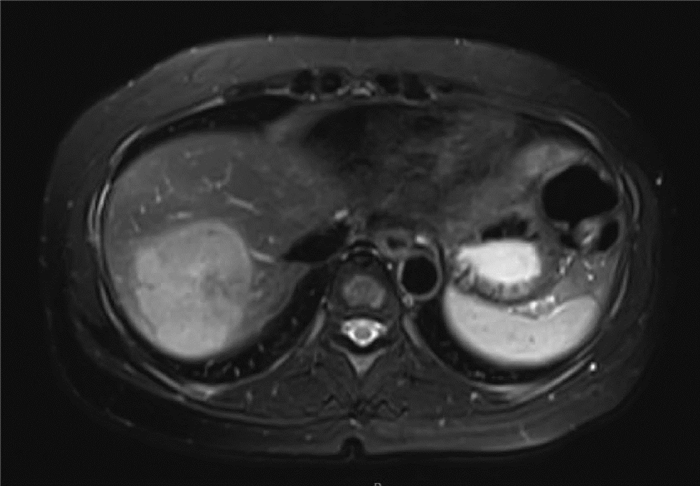

ATP7B基因复合杂合突变合并妊娠期急性脂肪肝1例报告

杨丹, 张翠薇, 邓明明

2022, 38(1): 167-169. DOI: 10.3969/j.issn.1001-5256.2022.01.027

摘要(968) HTML (376) PDF (3181KB)(66)

摘要: